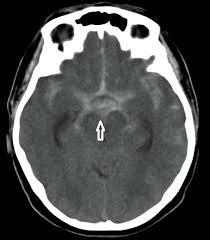

Subarachnoid hemorrhage- blood in cisterns

Epidural vs. subdural hemorrhage appearance on CT